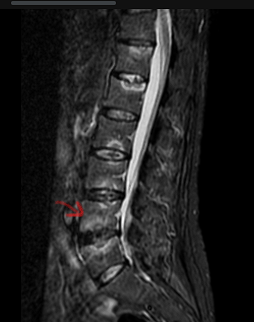

Achado da seta?

Sinal de Romanus.

Edema da medular, de canto, junto à entese. Cronicamente tem-se lipossubstituição/irregularidade.

Paciente com diagnóstico de Spa. Qual achado da seta?

Espondilodiscite de Anderson.